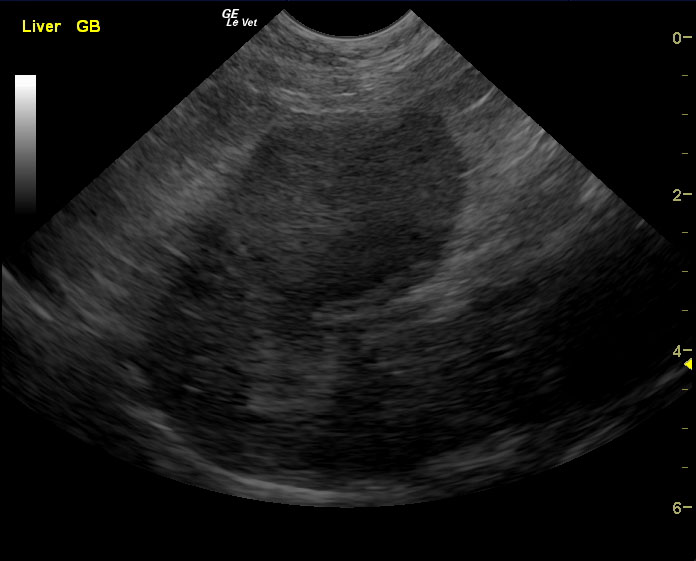

A 10-year-old, SF DSH cat was presented for acute onset vomiting and dehydration. Abnormalities on physical examination were icterus and dehydration. Pyuria with low urine SG was present on urinalysis. Urine culture was negative for bacterial growth after 24hrs. CBC and serum biochemistry showed marked leukocytosis with left shift and azotemia. Diffuse intestinal ileus was evident on survey radiographs.